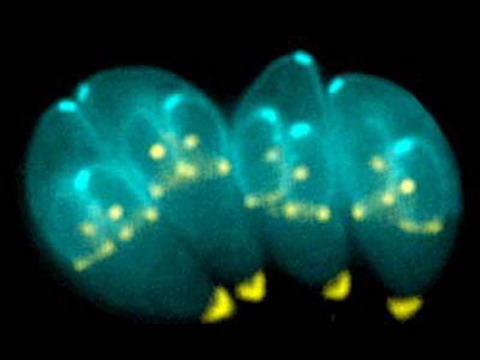

Ký sinh trùng Toxoplasma gondii: Loài ký sinh trùng hình lưỡi liềm này thường xâm nhập vào hệ thống thần kinh trung ương của con người. Con người bị nhiễm chúng do ăn thịt chưa nấu chín hoặc do tiếp xúc với phân mèo bị nhiễm bệnh. Hầu hết mọi người đã tiếp xúc với ký sinh trùng này một lần và sinh ra kháng thể miển nhiễm với nó. Nhưng một vài cá nhân có hệ miễn dịch yếu và cả bào thai có thể bị ảnh hưởng nghiêm trọng dẫn đến tử vong do nhiễm bệnh... Triệu chứng nhiễm: cúm, sốt, ớn lạnh, mệt mỏi, đau đầu.